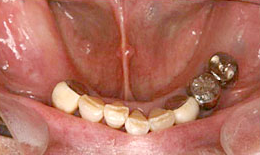

治療後

下顎

インプラントを4本埋め込んで、セラミックスクラウンを被せた

右下・左下

ハイブリッドクラウン

67,000×4=268,000円(税抜)